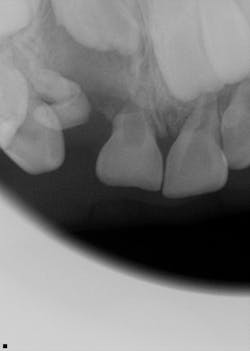

A healthy 7-year-old male presents for his new-patient exam. A radiolucency was noted in the no. 7 area on the panoramic radiograph; subsequent occlusals were referred to for a better view where the lesion appeared to focalize around the coronal portion of no. 7. Furthermore, there was an ill-defined radiopacity within the osseous tissue, under the area where primary tooth D would be located. The area was not tender to palpation nor was there any expansion noted in the vestibular area. Mom reported that the patient had trauma to the area a few years back while playing.

In this particular case, the patient was referred to an oral surgeon, who removed a root fragment of what was assumed to be tooth D as well as another piece of random deformed tooth structure. The cyst, along with what appeared to be tooth no. 7 (deformed), was surgically enucleated and the specimen was sent off for biopsy. Results came back as a benign dentigerous cyst. Tooth no. 8—although rotated—appeared to be unaffected.

The patient is being seen by an orthodontist for early interventional orthodontics; treatment options for replacement of tooth no. 7 are being considered as part of his long-term treatment plan.